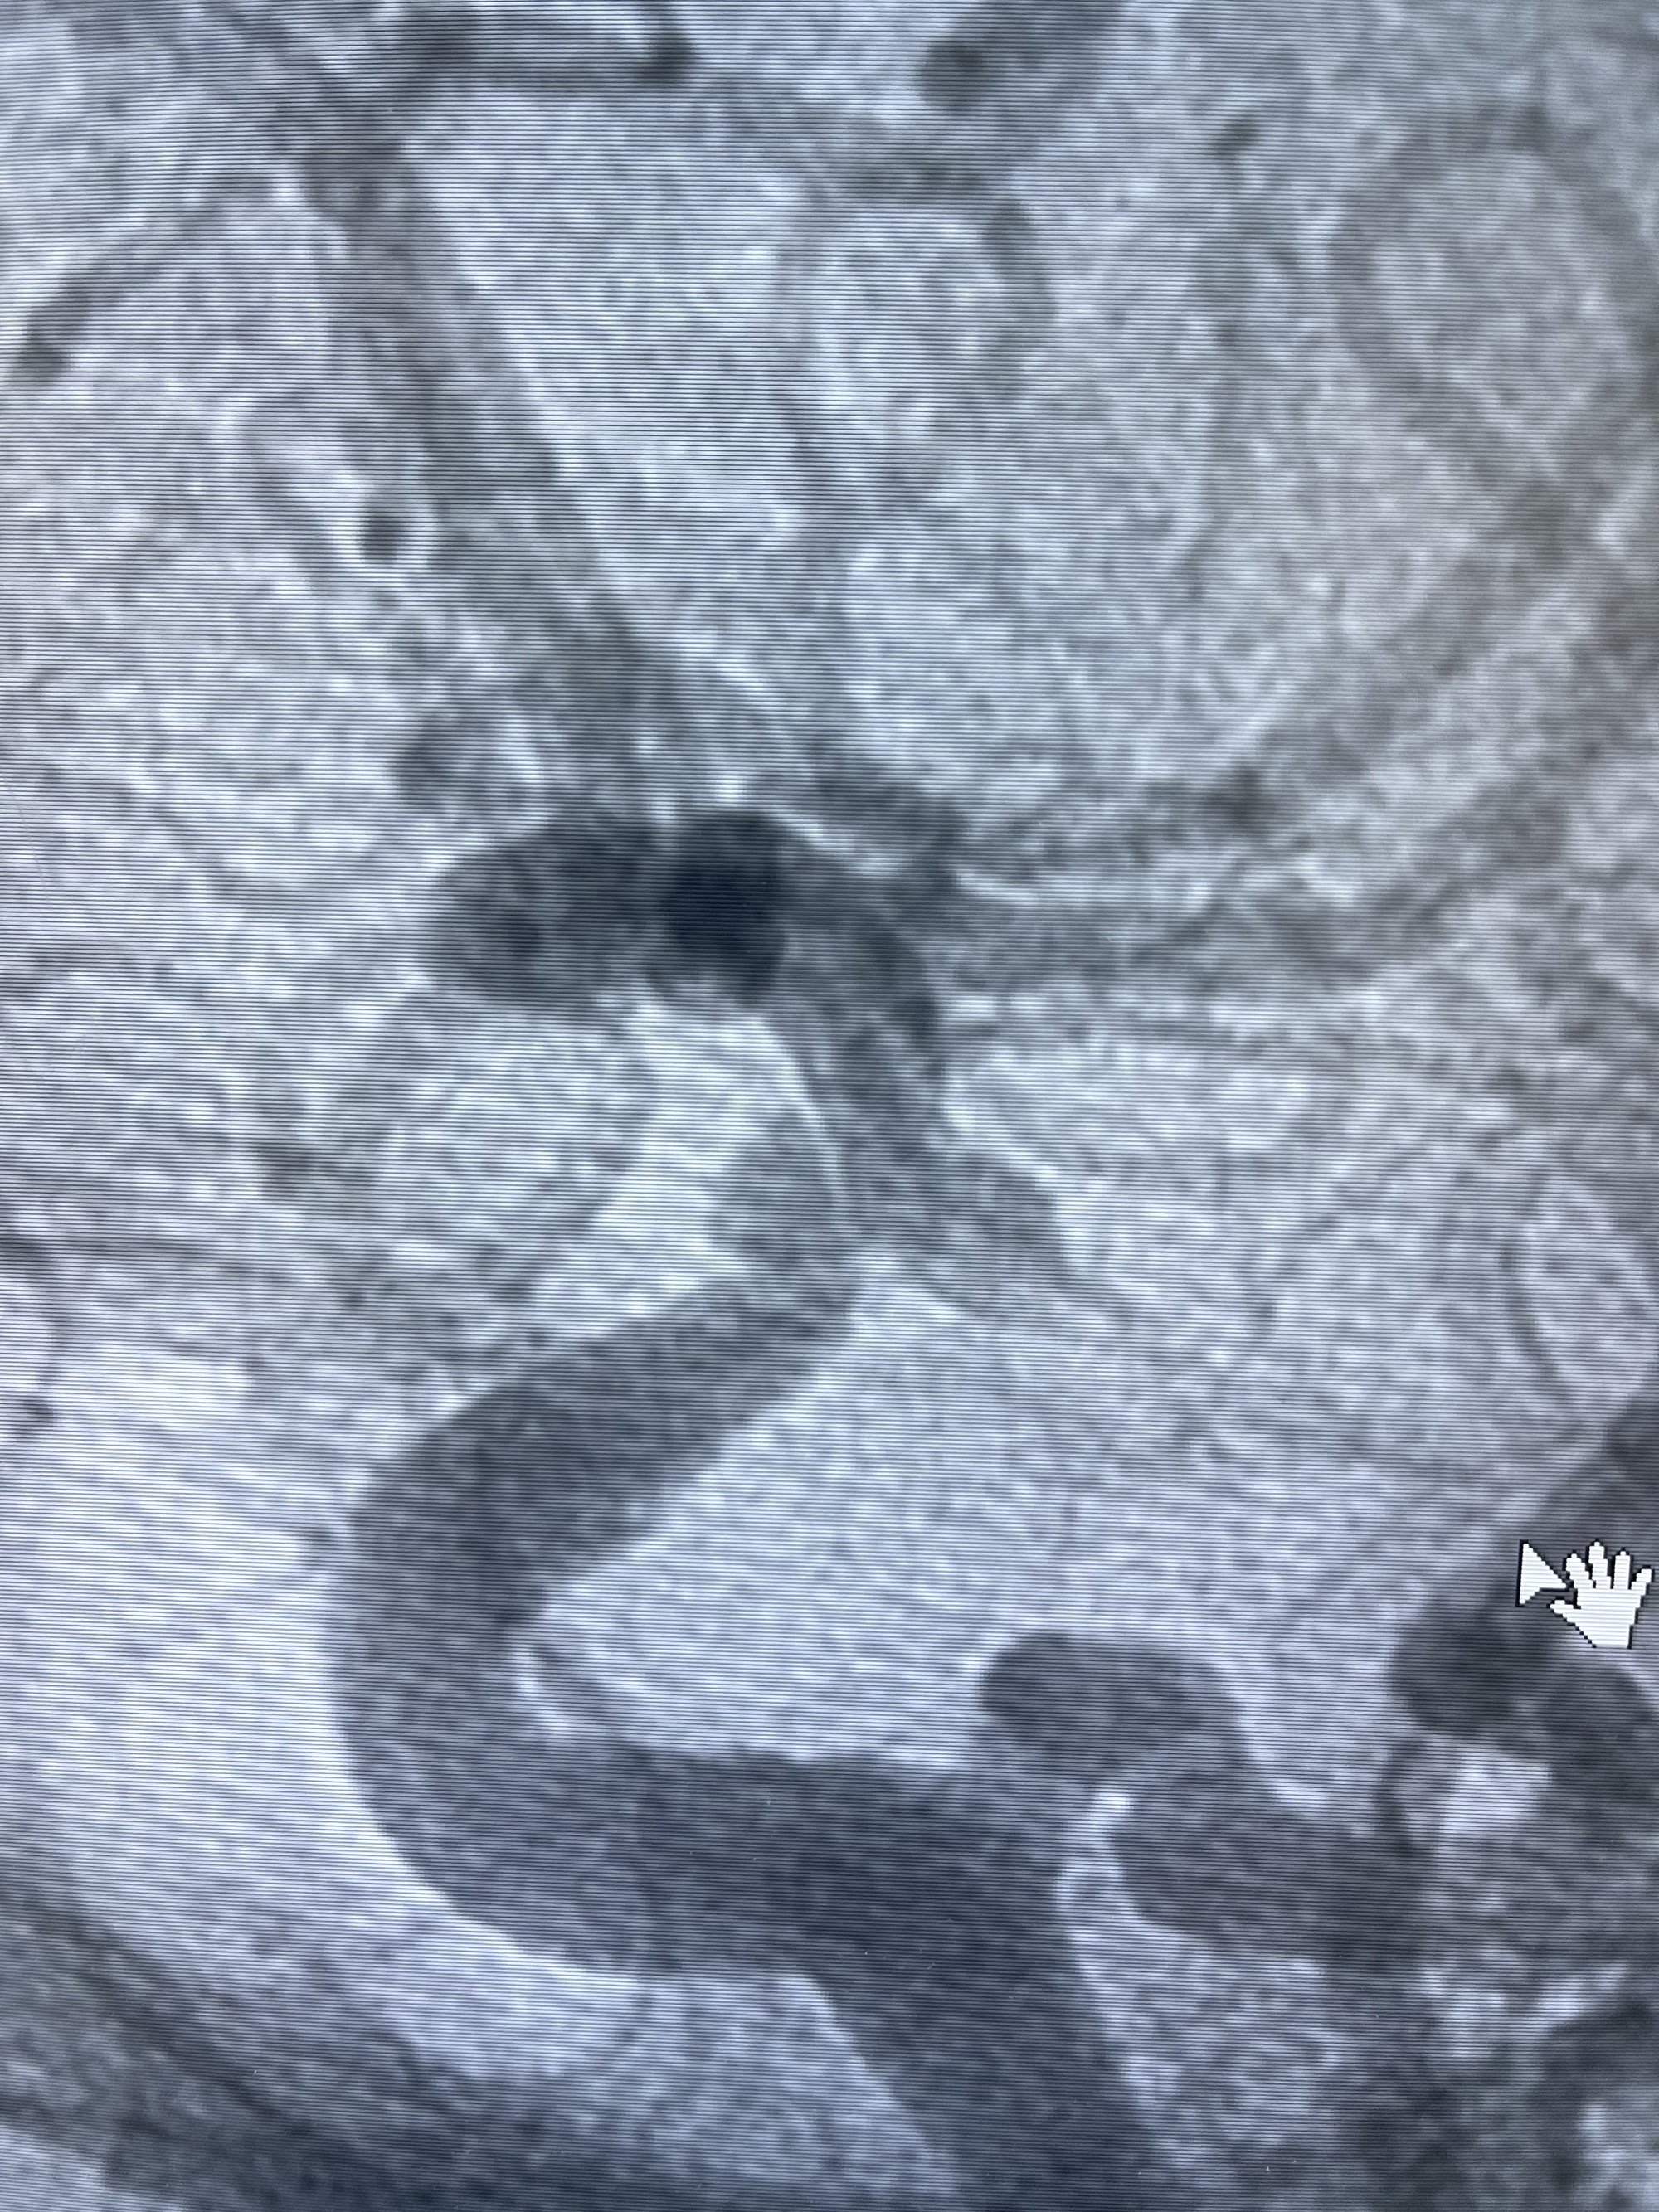

3.右侧颈内动脉眼动脉段近后交通动脉处重度狭窄伴前壁不规则动脉瘤

1.箭头处为右侧颈内动脉后交通动脉处重度狭窄,狭窄前壁为不规则动脉瘤;